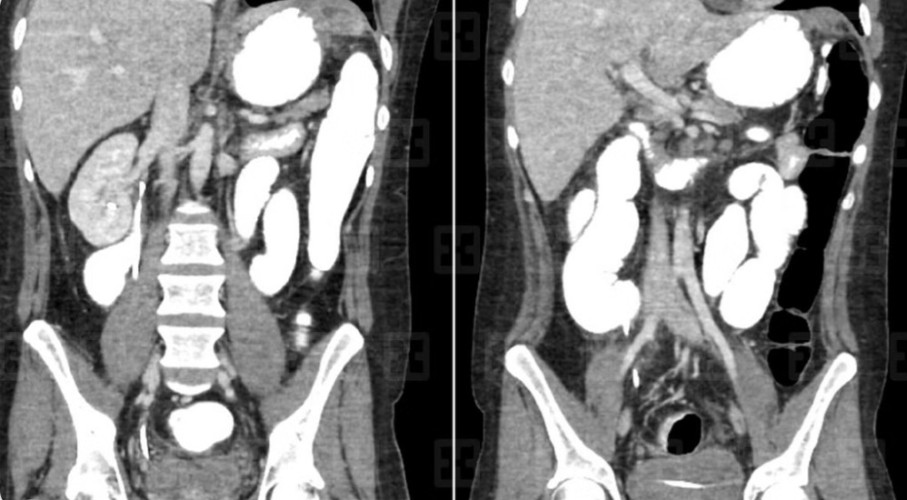

وأوضحت الصور الطبية ومناظير استكشاف البطن، أن الورم منتشر ومتشعب إلى أكثر من 7 من الأعضاء الداخلية لبطن المريض؛ مسببًا انسدادًا كاملًا في موضعين بالاثني عشر، إضافة إلى تمدده إلى جدار البطن والأمعاء والمرارة والجزء السفلي من المعدة وشحم البطن والحالب الأيمن، ومع هذا الانتشار الواسع للورم الذي بلغ وزنه 3 كجم، بدا وكأن التدخل الطبي سيقتصر على تقديم العلاج التلطيفي؛ لكن الفريق الطبي وضع خطة علاجية دقيقة، وأخضع المريض لواحدة من أعقد العمليات التي أجريت في المنطقة الشرقية، وتم فيها استئصال جزأين من الاثني عشر في حالة نادرة، كما تم استئصال الأورام المنتشرة أسفل المعدة، وفي المرارة وشحم البطن والأمعاء الدقيقة وجدار البطن وجزء من الكبد وجزء من الحالب مع زراعة دعامة للمنطقة المتضررة منه، ومن ثم قام الفريق الطبي بتوصيل القولون مع الأمعاء الدقيقة، وكذلك توصيل الجزء الثاني من الاثني عشر مع الجزء الرابع منه، وأخيرًا توصيل المعدة مع الأمعاء الدقيقة.